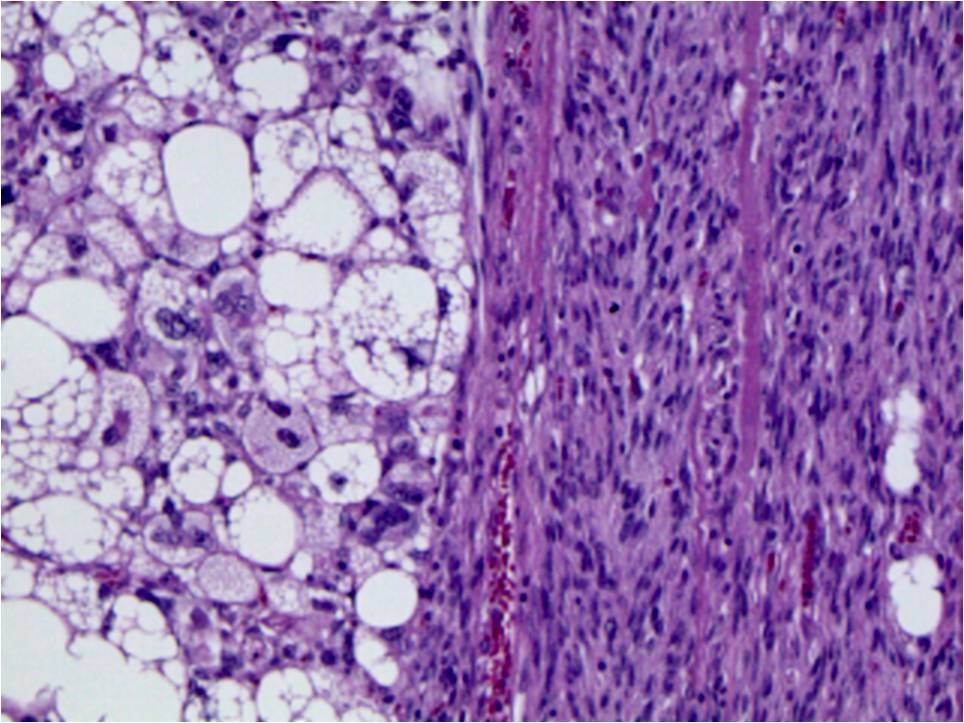

Microscopic Pathology

• Well differentiated liposarcoma (Fig. 15) with a sudden transition to a non-lipogenic sarcoma at least in several millimeters (Fig. 16)

Fig. 15 & 16 Microscopic Pathology. Medium magnification photographs demonstrate fibrous bands with enlarged hyperchromatic spindle cells admixed with

adipose tissue corresponding to well-differentiated lipomatous tumor (Fig. 15) and sudden transition between well differentiated liposarcoma to a non-lipogenic spindle cell sarcoma (Fig. 16).